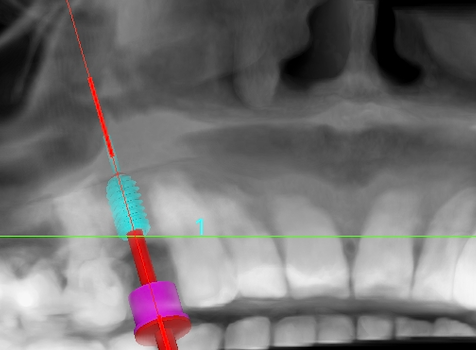

A middle aged foreign female patient booked an appointment at our Big Smile Dental Clinic & Prosthodontic Center, Kathmandu, Nepal. Upon examination she had missing upper right 1st premolar tooth. After thorough examination and counseling, we planned for dental implant.

Dental implant was placed on planned position successfully. Procedure was done by experienced specialist and treatment was painless and uneventful. Patient was comfortable and happy after successful placement of dental implant. Next appointment has been appointed after 4 to 6 months for prosthesis procedure.